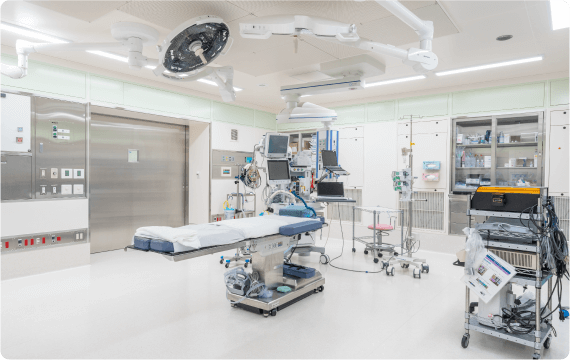

手術・麻酔

シムラ病院では増え続ける手術件数に対応できるよう、手術室を3部屋に増設しました。整形外科領域においては、広島大学四肢外傷講座と連携し、一般外傷から難易度の高い外傷手術まで幅広い整形外傷手術医療を提供しています。また、低侵襲で最先端の高度診療技術を活用した脊椎手術には自信があり、人工関節・スポーツ外傷に至るまで様々な分野における質の高い手術をお約束いたします。

シムラ病院では増え続ける手術件数に対応できるよう、手術室を3部屋に増設しました。整形外科領域においては、広島大学四肢外傷講座と連携し、一般外傷から難易度の高い外傷手術まで幅広い整形外傷手術医療を提供しています。また、低侵襲で最先端の高度診療技術を活用した脊椎手術には自信があり、人工関節・スポーツ外傷に至るまで様々な分野における質の高い手術をお約束いたします。

外科領域においては広島大学病院と連携し、呼吸器外科(肺)手術、乳腺手術、一般外科手術も行っており、多くの患者さまに喜んでいただいています。